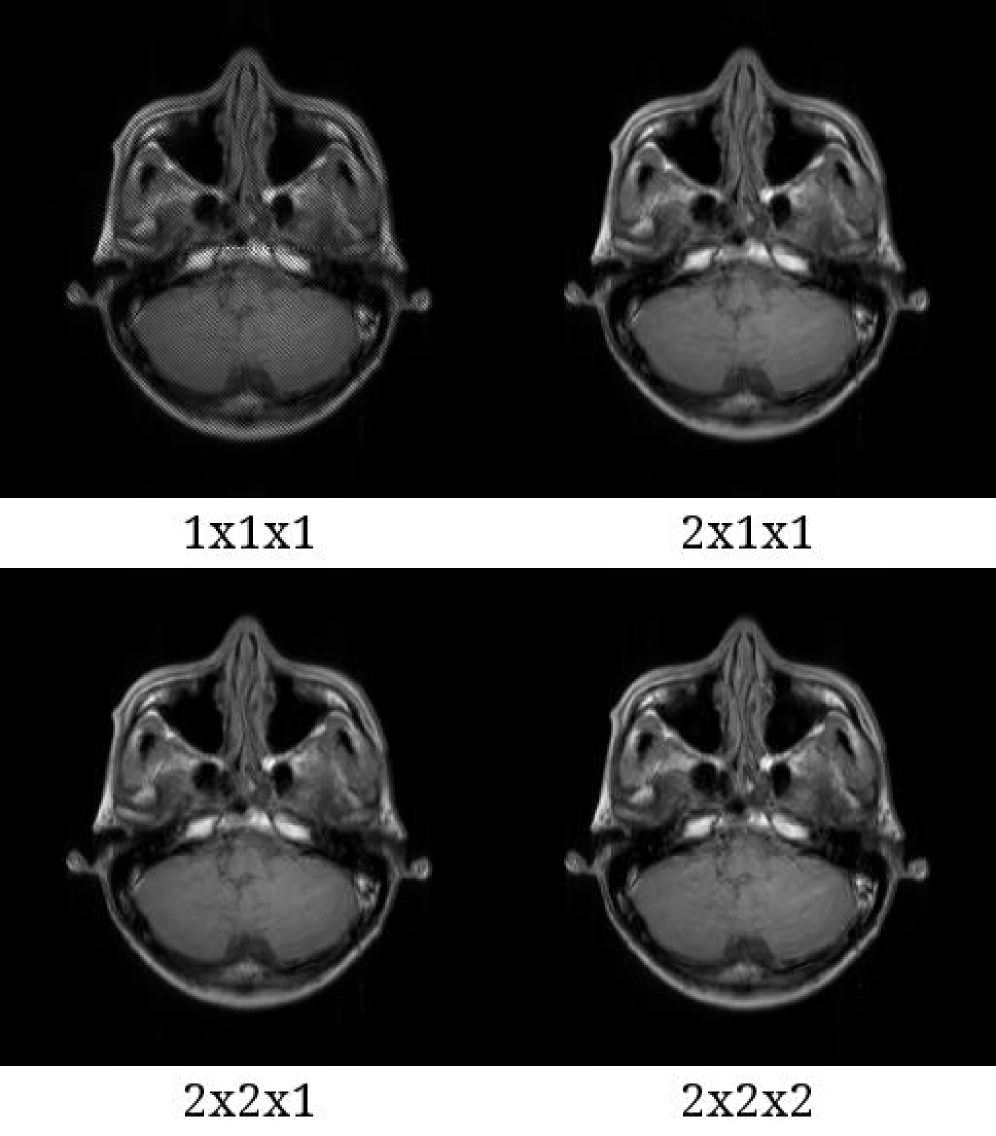

Figure S1. Reconstructed images and their error images in the case of a T1W sequence. (a) Reconstructed images using the brain phantom with reference (ungrouped), 64 clusters, 128 clusters and 256 clusters. (b) Errors between the reference and grouped images. The errors were multiplied by 10. As shown in the error images, all image with 128 and more clusters were visually close to the reference image. Abbreviations: T1W, T1-weighted.

[Uncaptioned image]